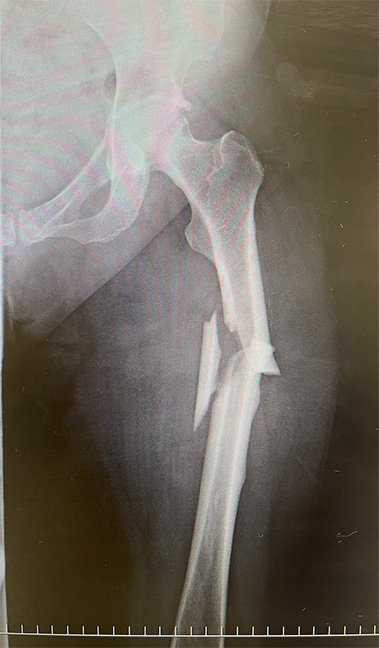

AFFは、大腿骨の転子下から顆上部にかけての骨幹部に発生する骨折で、その特徴として、外傷が軽微であること、骨折線が横走または短斜走であること、外側皮質の肥厚(beaking)を伴うことなどが挙げられる 5)図1)。完全骨折に至る前に、大腿や鼠径部の疼痛(前駆症状)を訴えることが多く、両側性に発生する傾向がある。

図1 71歳女性の左大腿骨非定型骨折(自験例)